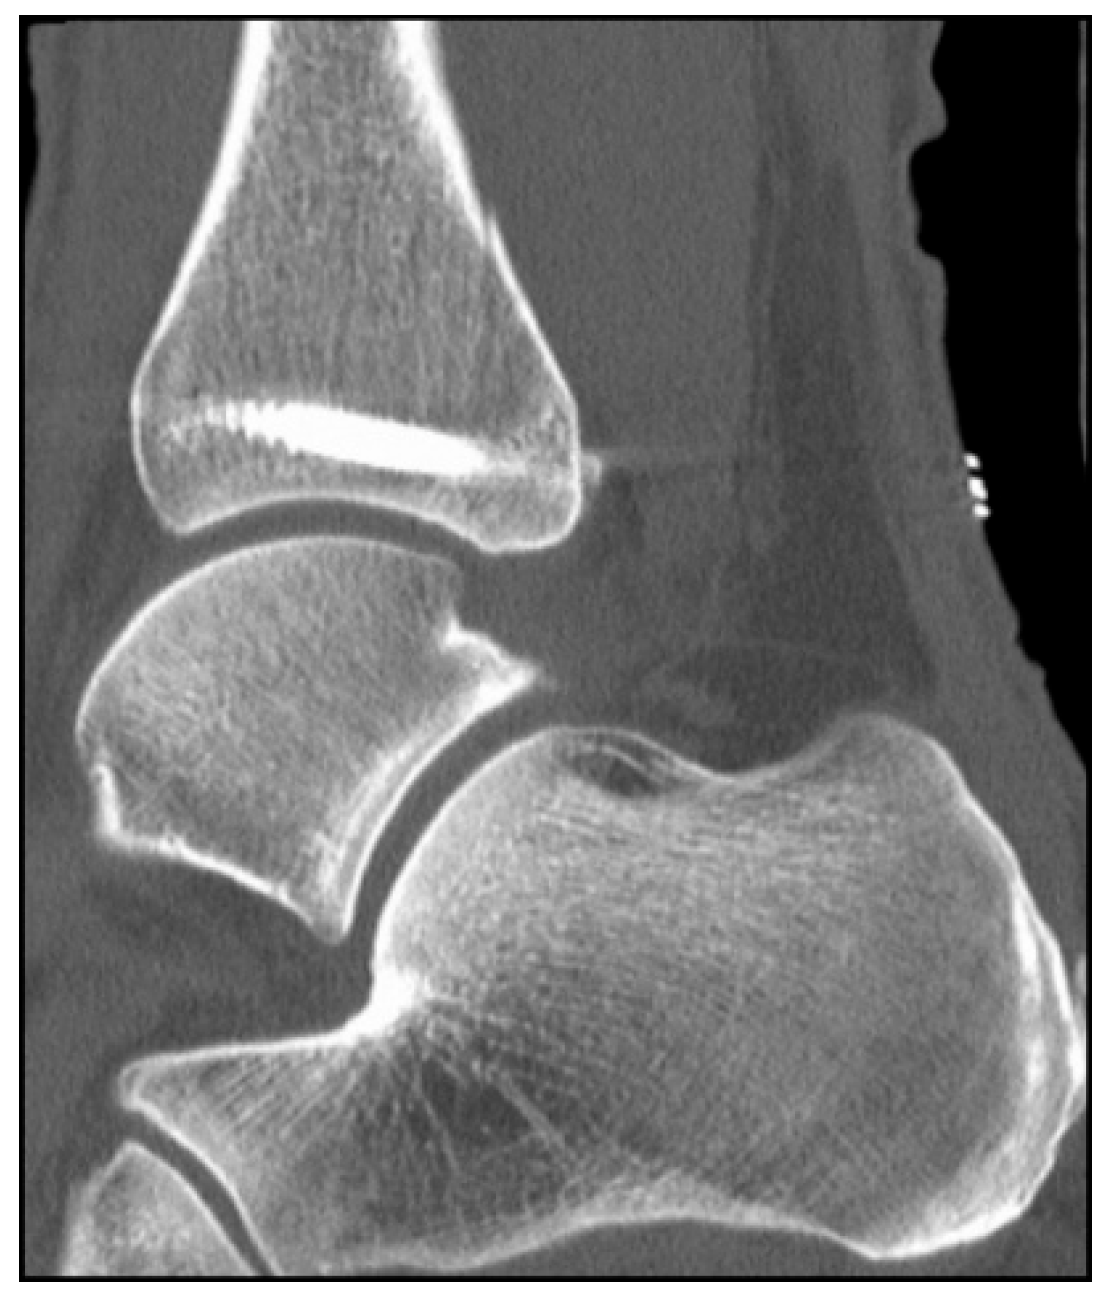

5.2. Inside-Out Fixation of the Posterior Malleolus Using a Headless Double-Threaded Compression Screw

5.3. Specific Considerations on Double-Threaded Screws in the Management of Complex Ankle Fractures

9. Follow-Up